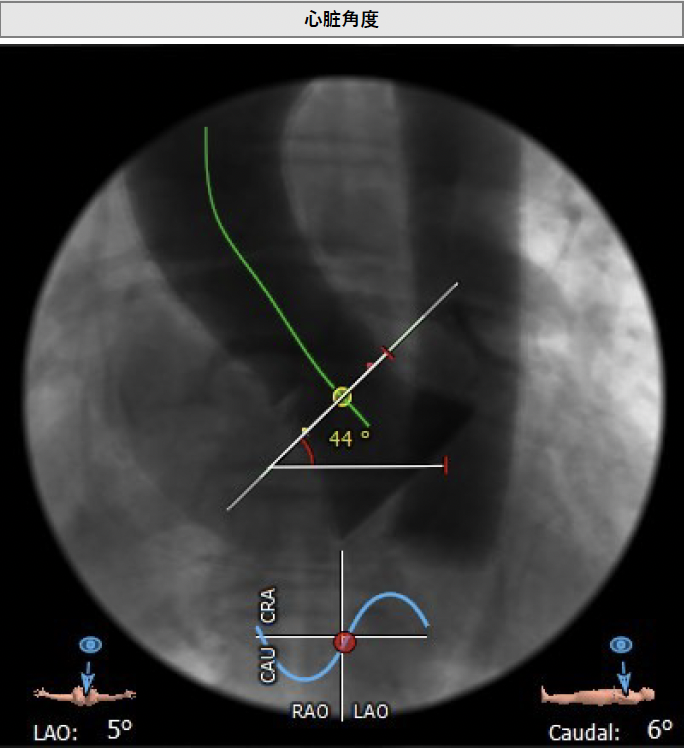

主动脉瓣角度 44°